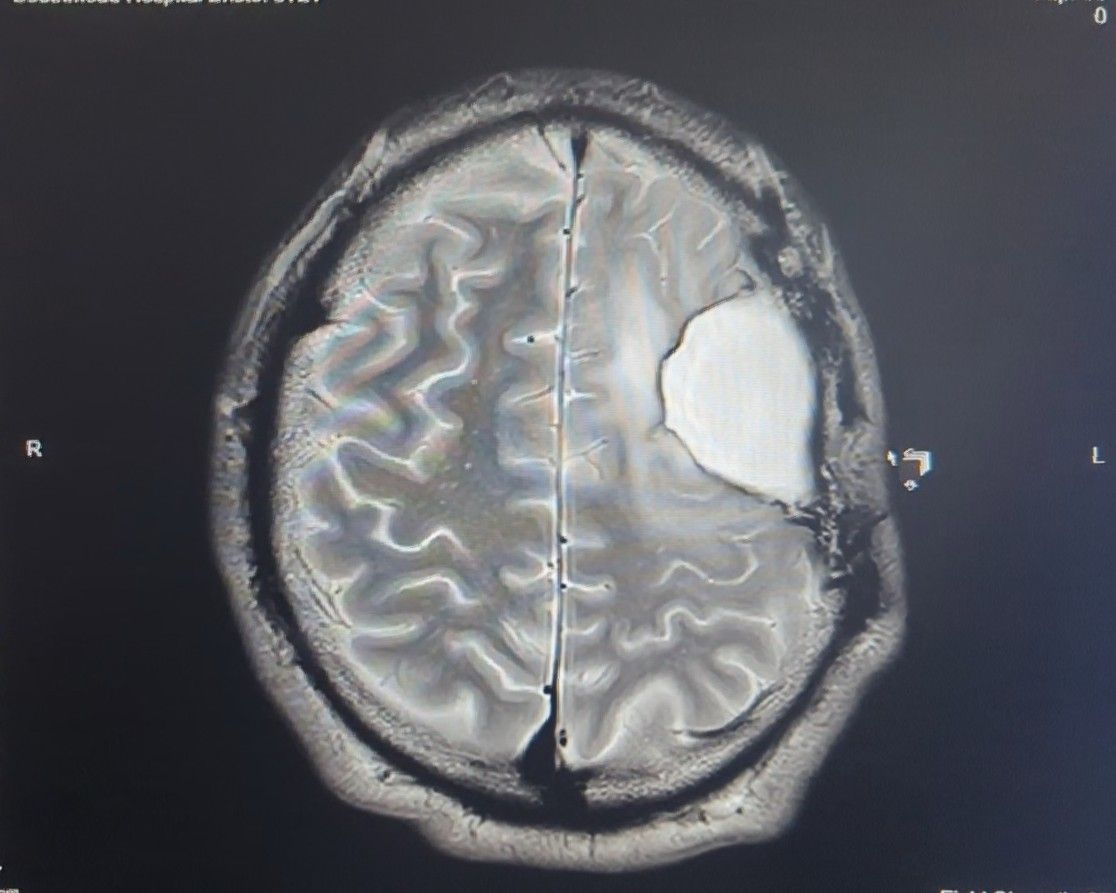

After a road traffic accident, a pear-sized Glioma–a type of brain cancer was discovered as an unexpected and unwelcome guest in my head

The Story, So far in pictures…